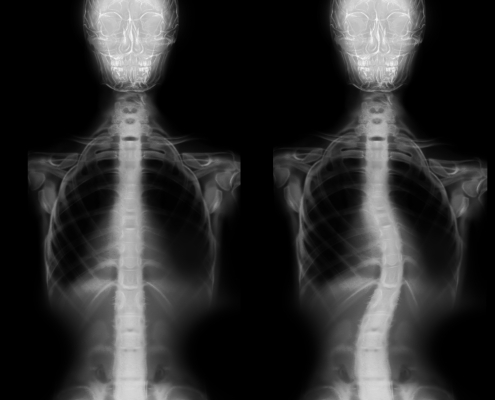

- Skolyoz, kifoz